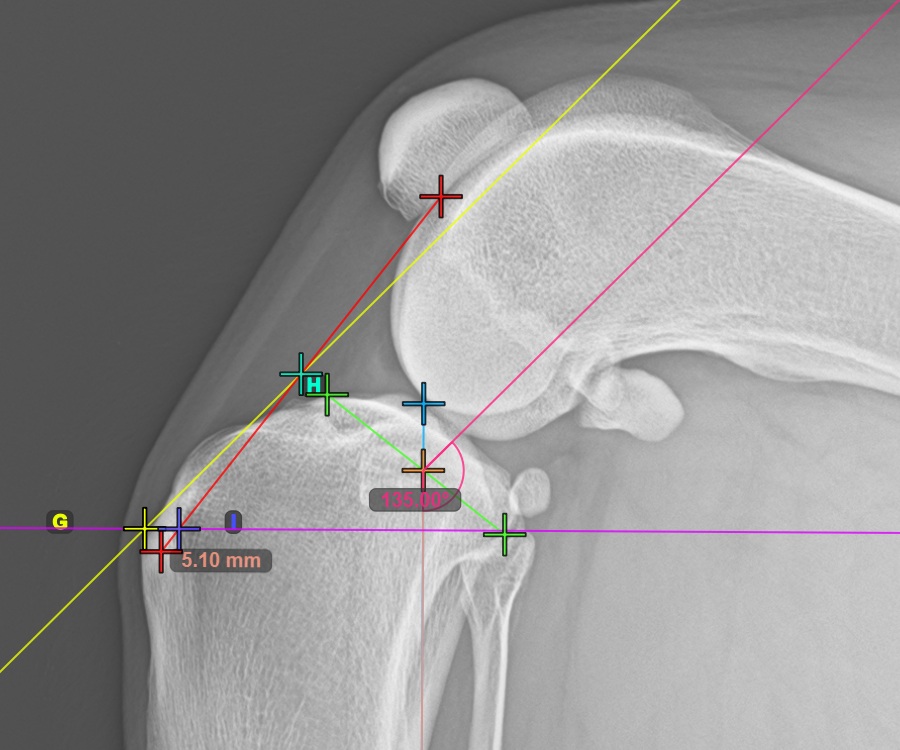

A TTA Rapid típusú TTA mérés befejezéséhez jelölje meg a Crista Tibiae (Tuberositas Tibiae) legtávolabbi (most dorsal) pontját. A Tuberositas Tibiae és az automatikus TTA Rapid segédvonalak közötti távolság adja a TTA eljáráshoz szükséges korrekció mértékét.

A lenti kép a tibia taréj legkiemelkedőbb pontjának, a tibialis gumónak a szokásos elhelyezkedését ábrázolja.